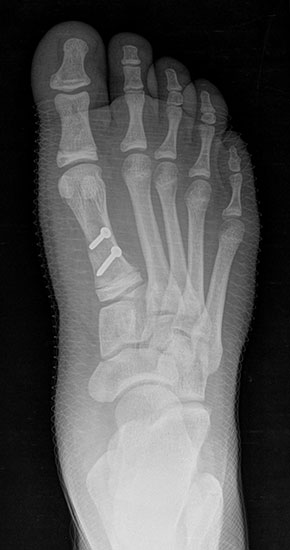

Bezüglich der Operationstechniken wird von früher häufig durchgeführten alleinigen Weich­teileingriffen am Großzehengrundgelenk aufgrund hoher Rezidivraten abgeraten 15. Die Operation nach Mc Bride mit lateralem Release, Exzision des lateralen Sesambeins, Abtragen der Pseudoexostose, Sehnenetransfer des M. adductor hallucis und mediale Kapselraffung zeigte unbefriedigende Mittel- und Langzeitergebnisse 16. Die Cerclage fibreux (mediale Kapselraffung) und das laterale Kapselrelease wird heute in Kombination mit einem knöchernen Eingriff angewendet. Bezüglich des Einsatzes von minimalinvasiven Operations­techniken vor Wachstumsabschluss liegen bisher keine Daten vor. Alle Osteotomien lassen sich nach Bedarf miteinander kombinieren. Es ist darauf zu achten, dass Osteotomien keine offenen Wachstumsfugen verletzen.

• Medial zuklappende Grundphalanxosteotomie nach Akin 17

• Subcapitale distale Chevron Osteotomie nach Austin 18

• Diaphysäre Osteotomie

• Scarf 19

• Ludloff 20

• Proximale Metatarsale I Osteotomien 21

• medial aufklappend – verlängernd

• lateral zuklappend – verkürzend

• bogenförmige Crescentic Osteotomie

• proximale Chevron Osteotomie

• proximale Verschiebeosteotomie

• medial aufklappende Cuneiforme I Osteotomie 1522

• Wachstumslenkung: Hemiepiphysiodese der lateralen Basisfuge am Metatarsale I  23

• Nach Schluss der Wachstumsfugen: TMT I Arthrodese nach Lapidus 2425